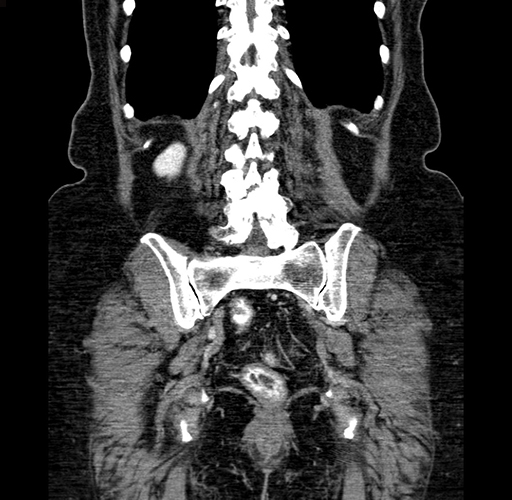

Pre-Chemo: Axial Venous

Axial Venous